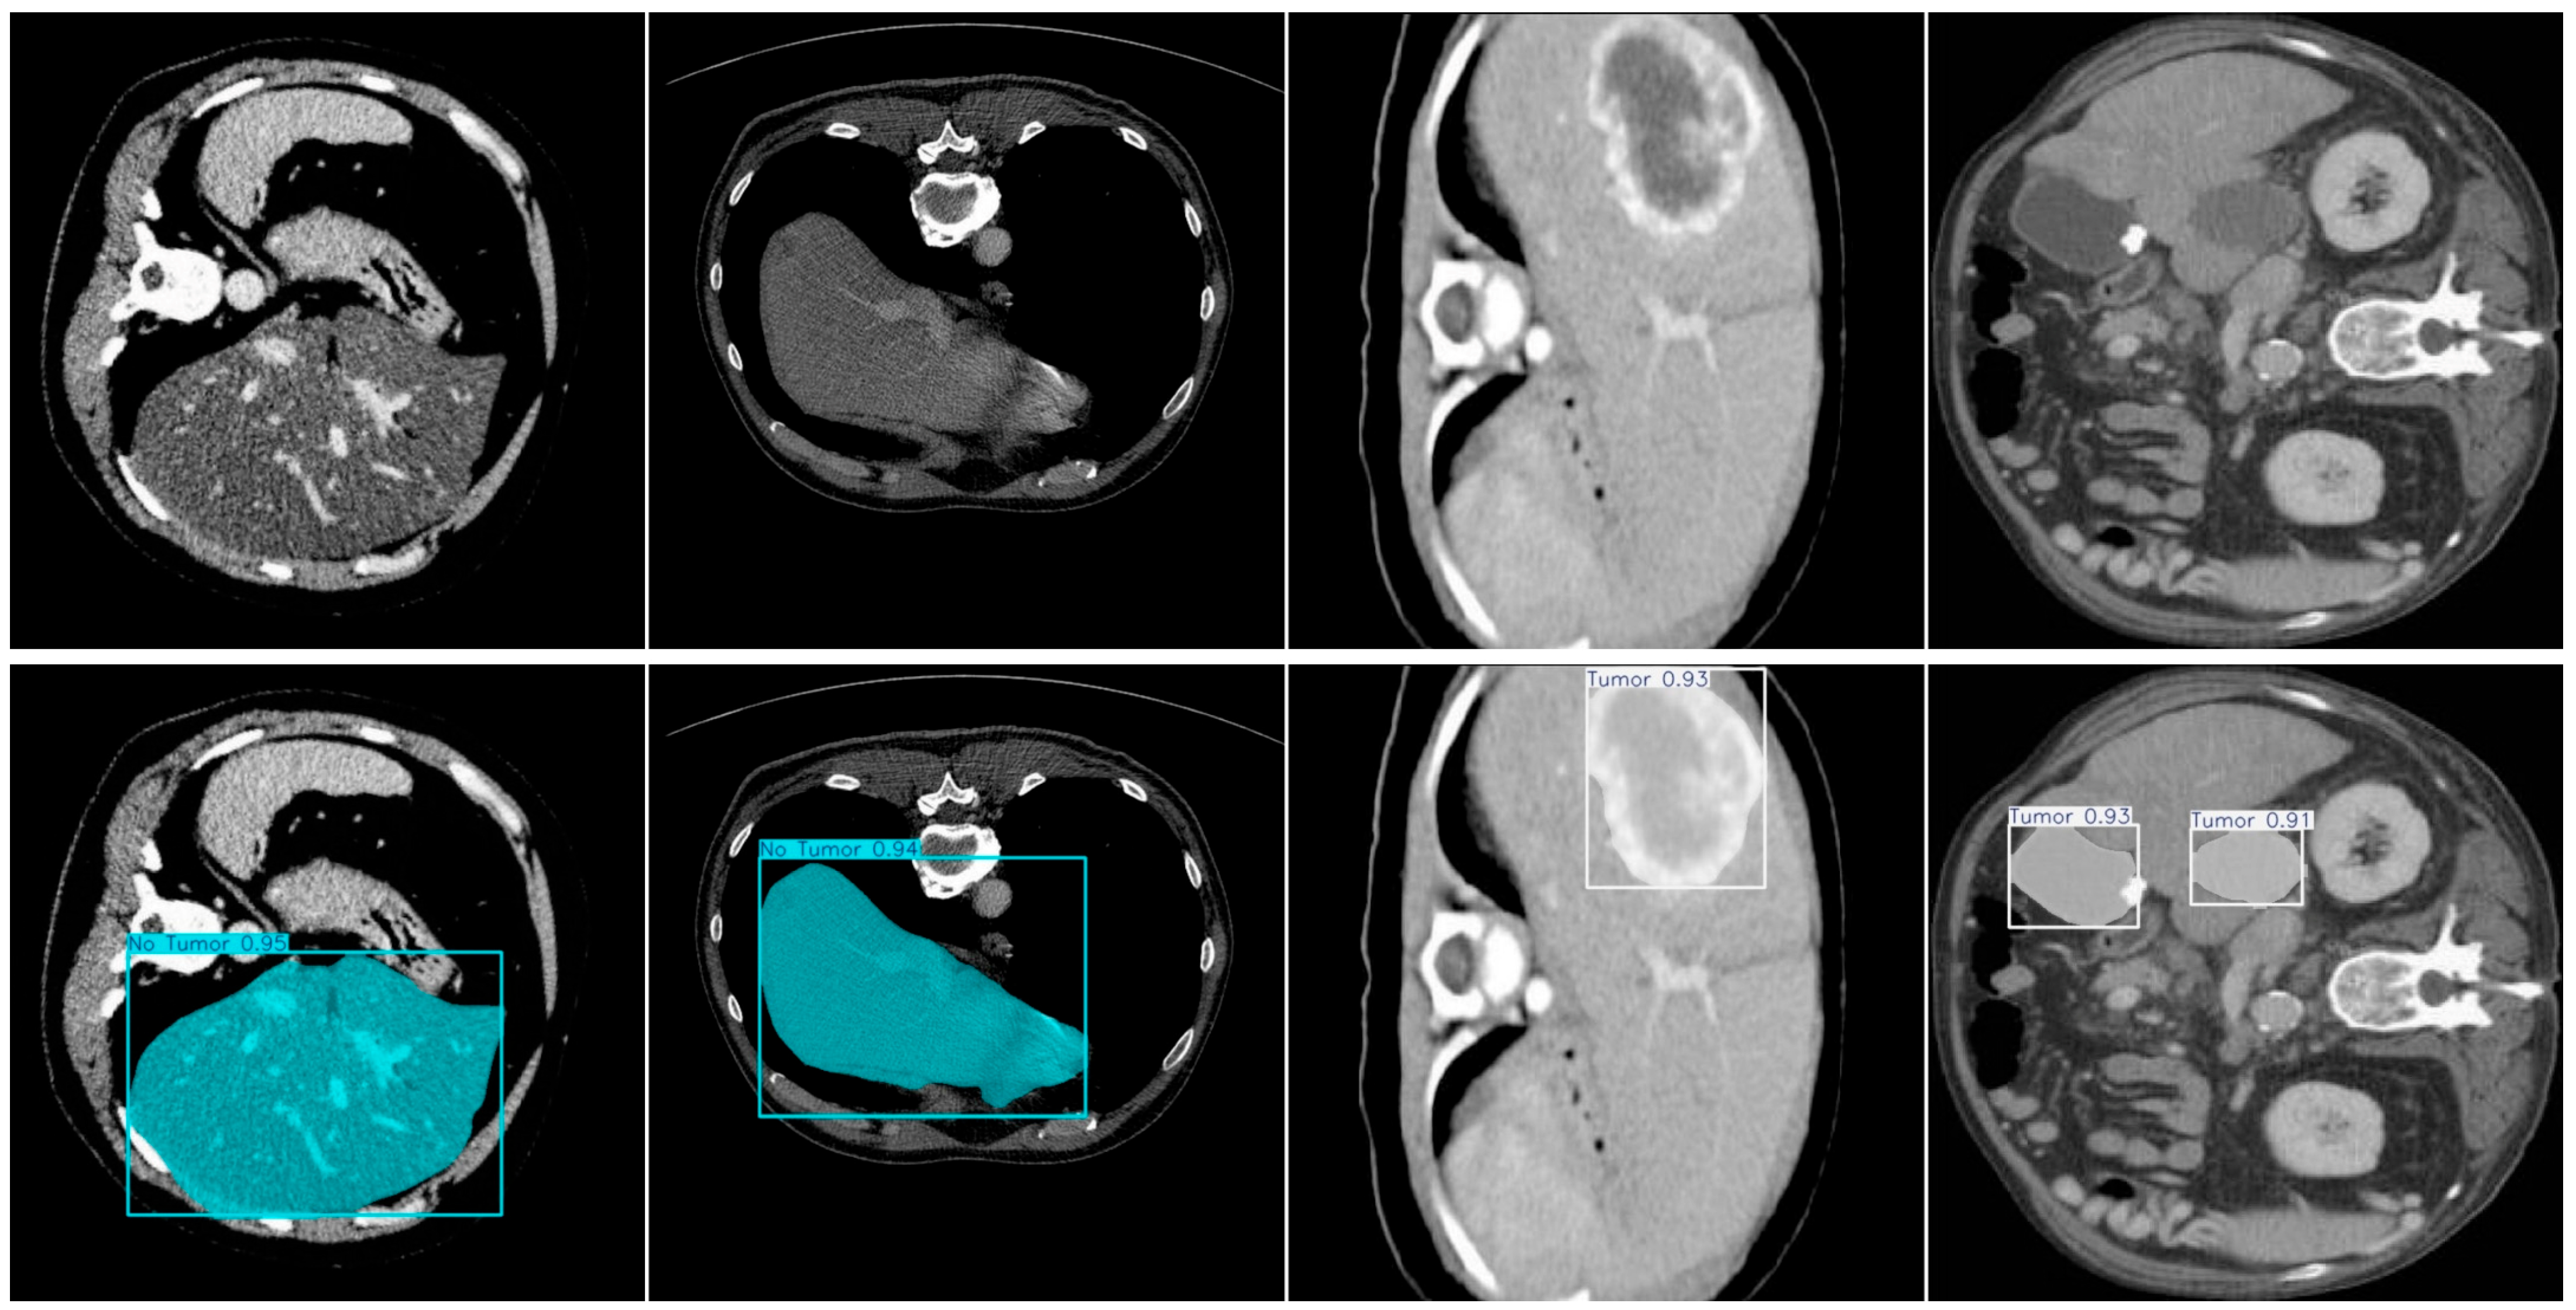

4.7. Supplementary Experiment

- Roboflow. Project 5C Liver Tumor > Roboflow Universe. Available online: https://universe.roboflow.com/segmentasiliver/project-5c-liver-tumor-aikum (accessed on 11 September 2025).